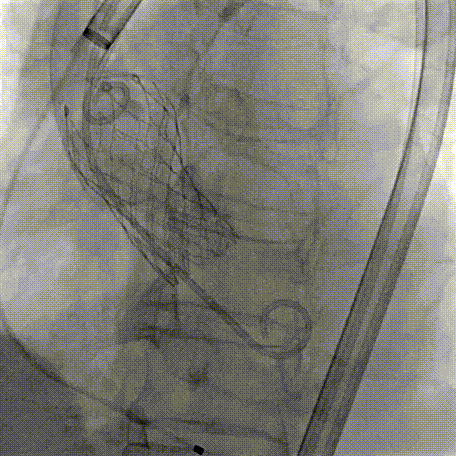

Step 5.瓣膜定位与释放:高起始位逐渐向下推送保持良好同轴性,无位移

Step 6.工作位观察:真实瓣环下方2mm,位置合适,决定释放,一次完成

Step 7.瓣膜脱钩:脱钩稳定无位移

Step 8.最终造影:真实瓣环下方3mm标准位,完全同轴,轻微反流,猪尾撤出后反流完全消失